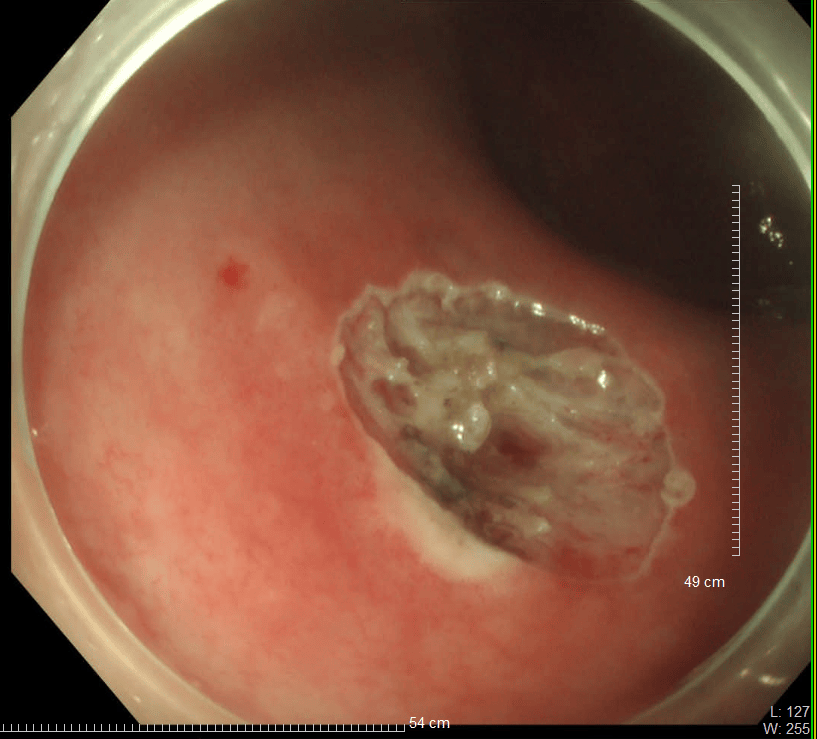

36歲的王先生在蘇州高新區人民醫院行胃腸鏡檢查時,發現直腸裡有1個息肉和2個黏膜下半球型隆起,表面光滑、顏色發黃,大小直徑約1.0cm,當時便做了超聲內鏡檢查,顯示2個隆起的腫物位於直腸黏膜下層,可能是神經內分泌腫瘤,1個粘膜層隆起的息肉可能是腺瘤腫瘤。消化科團隊立即為王先生進行了腸鏡下黏膜剝離術切除了2個粘膜下腫物,同時進行了腸鏡下粘膜切除術解決了1個腺瘤樣息肉,術後病理顯示:2個是神經內分泌瘤NET G1,切緣乾淨。1個管狀腺瘤伴低階別上皮內瘤變(屬於癌前病變),目前王先生恢復良好,已順利出院。

直腸神經內分泌瘤內鏡下治療的適應證包括腫瘤直徑<1 cm,侷限於黏膜或黏膜下層(T1期)的G1/G2級病變腫瘤。對直徑1-2cm的腫瘤,兼顧根治及功能保全,透過內鏡及影像學充分評估後選擇治療方式。內鏡下黏膜剝離術(ESD)是一項先進的內鏡下四級微創技術,醫生透過電刀,在內鏡下實現對胃腸道表淺病變的治癒性切除。